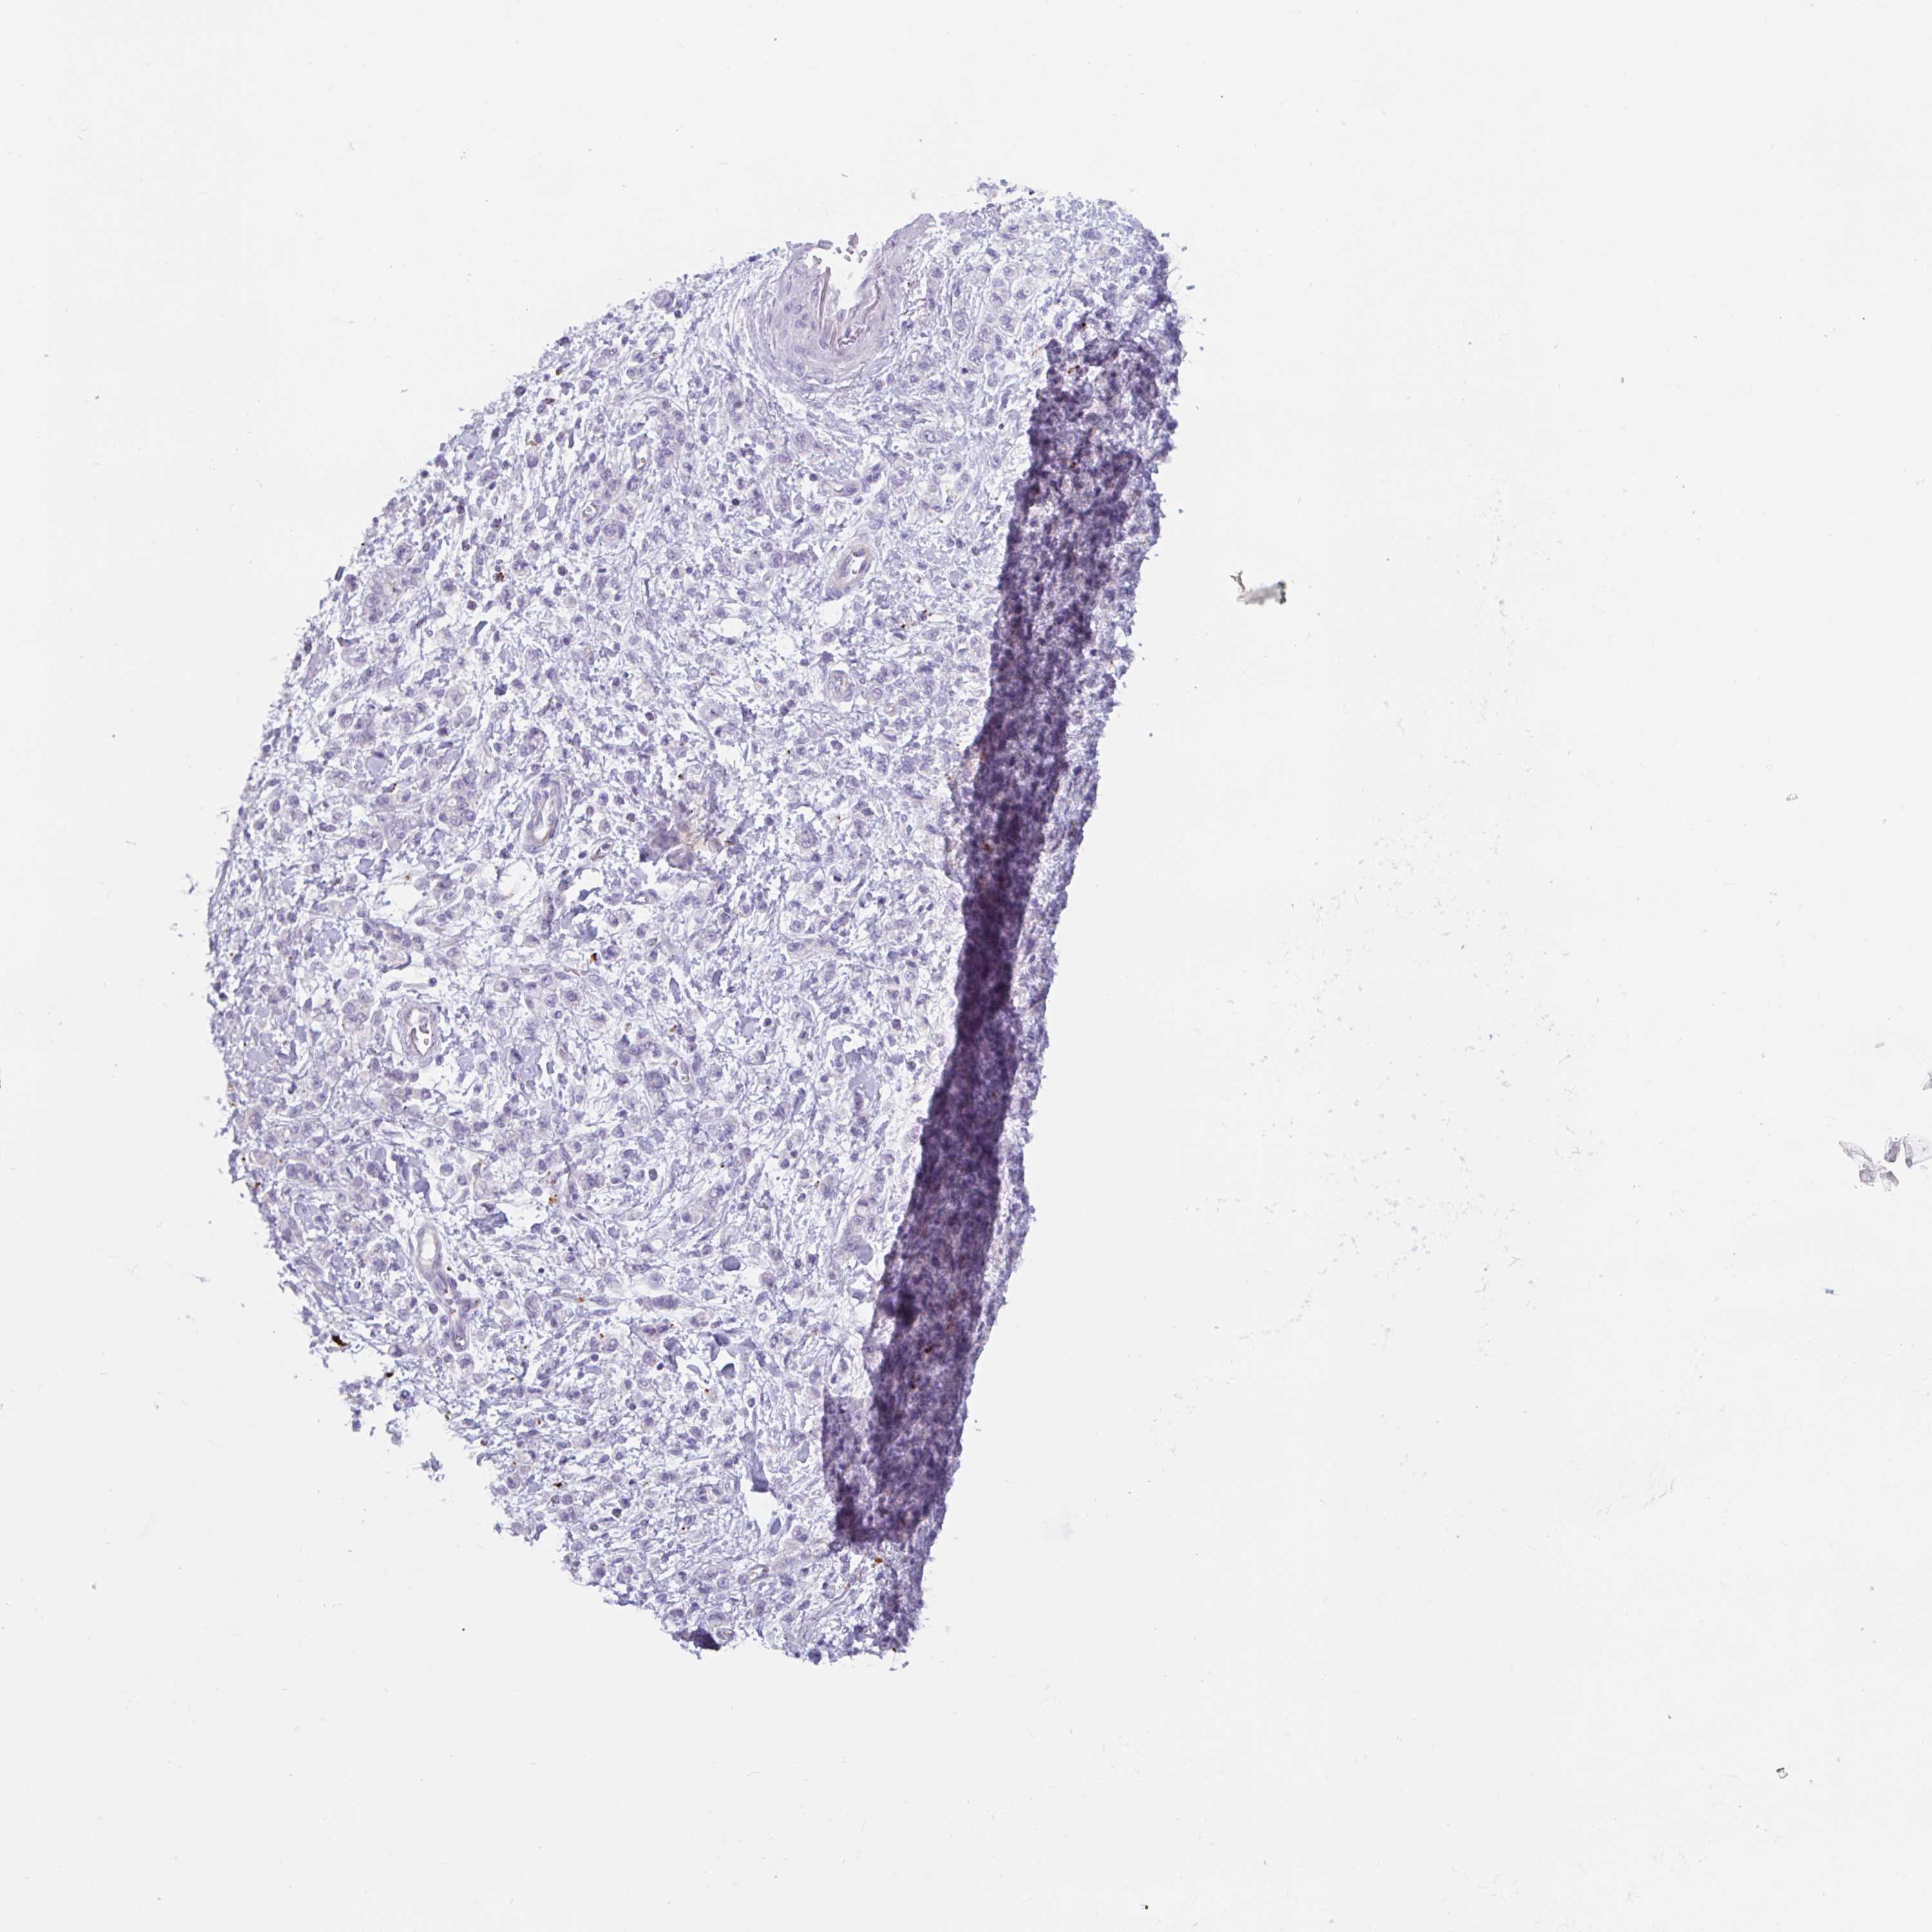

STOMACH CANCER - Protein expressioni

A mouse-over function shows sample information and annotation data. Click on an image to view it in a full screen mode. Samples can be filtered based on level of antibody staining by selecting one or several of the following categories: high, medium, low and not detected. The assay and annotation is described here.

Antibody stainingi

Antibody staining in the annotated cell types in the current human tissue is reported as not detected, low, medium, or high, based on conventional immunohistochemistry profiling in selected tissues. This score is based on the combination of the staining intensity and fraction of stained cells.

Each image is clickable and will lead to virtual microscopy that enables deeper exploration of all samples and also displays staining intensity scores, fraction scores and subcellular localization as well as patient and tissue information for each sample.

Antibody HPA051671

Antibody HPA053556

Staining

High

Medium

Low

Not detected

Intensity

Strong

Moderate

Weak

Negative

Quantity

>75%

75%-25%

<25%

None

Location

Nuclear

Cytoplasmic/membranous

Cytoplasmic/membranous,nuclear

Adenocarcinoma, NOS